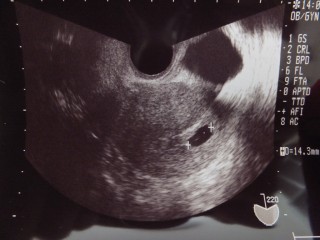

40歳で初の妊娠です。卵管通水検査をした週に妊娠しました。 先週は、ちいさな胎嚢だけみえましたが、今回は14.1㎜の胎嚢と卵黄嚢が見えました!来週には胎芽が見えるかなぁ、楽しみです!